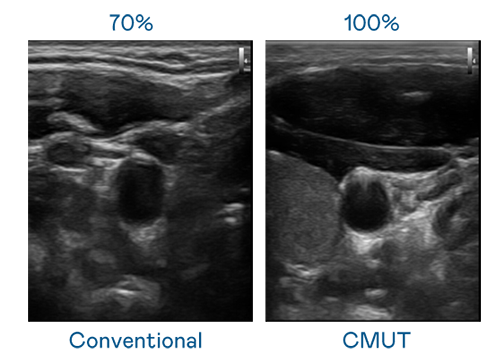

CMUT 技术是一种用电容式微机电元件来产生超音波讯号的技术。与传统 PZT 压电式技术相比,CMUT 频宽增加 30%,更宽频的超音波讯号让影像解析度大幅提升,是实现高影像品质医疗超音波扫描、促进精准医疗发展的关键技术。

超音波影像的解析度高低,首先取决于探头能发出的讯号频宽。彩霸王官网 CMUT 可提供高清晰的超音波讯号,提供高频宽、高灵敏度、影像纹理细节更高的超音波影像,协助医护人员缩短影像判读时间及利用精准的医疗影像进行诊断。